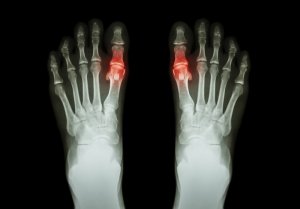

Gikt är ett tillstånd som orsakas av ackumuleringen av mikroskopiska kristaller av urinsyra i lederna. Dess kristaller formar bulor under huden eller ansamlas i urinvägarna.

Men då detta inte fungerar kommer urinsyrans nivå att öka markant. Kristaller formas och ackumuleras vid lederna, vilket orsakar en skarp smärta.

- Den drabbade leden är vanligtvis varm och röd (inflammerad). Den tenderar generellt också att vara känslig och svullen.